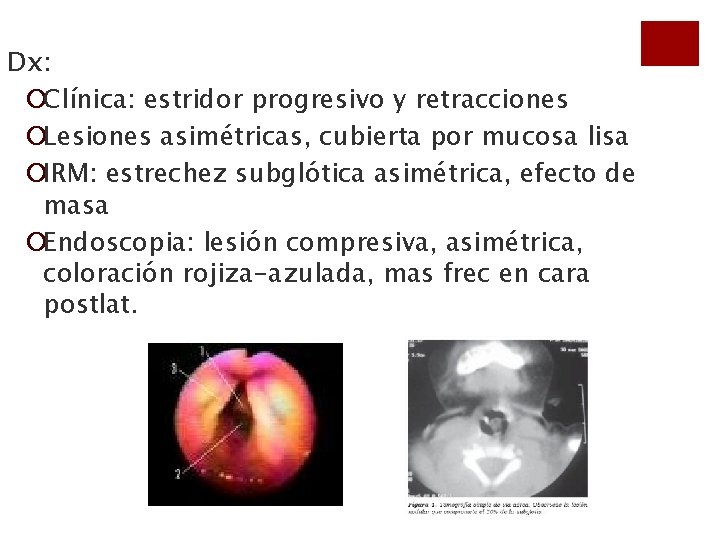

Dx: ¡Clínica: estridor progresivo y retracciones ¡Lesiones asimétricas, cubierta por mucosa lisa ¡IRM: estrechez subglótica asimétrica, efecto de masa ¡Endoscopia: lesión compresiva, asimétrica, coloración rojiza-azulada, mas frec en cara postlat.